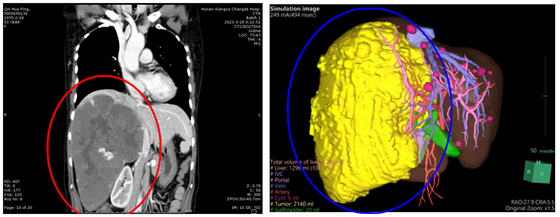

肝血管瘤是常见的肝脏良性肿瘤,多半没有症状,一般无需特殊治疗。近日,湘雅常德医院普外科一区(肝胆胰外科)接诊了一名反复发热合并贫血的巨型肝血管瘤患者,切除肝血管瘤直径...